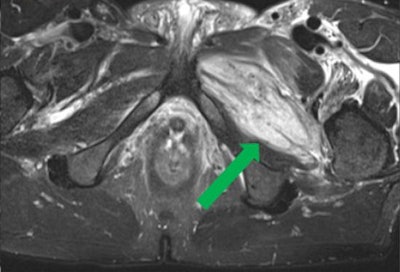

Coronal T2-weighted fat-suppressed MR image shows a partial tear of pectineus muscle in a 27-year-old football player who presented with hyperintense hemorrhage and tearing up to 50% of muscle fibers (green arrow); focal defect shows partial retraction of muscle fibers. Grade 2 strain (moderate partial muscle tear) was positive for significant fiber disruption, probably including some retraction, fascial injury, and intermuscular hematoma. All images courtesy of Dr. Valentin Sinitsyn; Dr. Maria Lisitskaya, PhD; and Dr. Sergey Khaykin, PhD, presented at the 2017 annual meeting of the ESSR.

Coronal T2-weighted fat-suppressed MR image shows a partial tear of pectineus muscle in a 27-year-old football player who presented with hyperintense hemorrhage and tearing up to 50% of muscle fibers (green arrow); focal defect shows partial retraction of muscle fibers. Grade 2 strain (moderate partial muscle tear) was positive for significant fiber disruption, probably including some retraction, fascial injury, and intermuscular hematoma. All images courtesy of Dr. Valentin Sinitsyn; Dr. Maria Lisitskaya, PhD; and Dr. Sergey Khaykin, PhD, presented at the 2017 annual meeting of the ESSR.The authors studied MRI data from 28 players who complained of groin pain to their team doctor and were referred for imaging between July 2014 and May 2016. The mean age of the cohort was 29.7 (range 25 to 34 years old). One of the co-authors, Dr. Sergey Khaykin, PhD, is a sports physician at FC Lokomotiv.